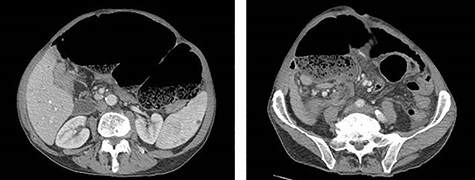

A 74-year-old male with past medical history of hypertension, coronary artery disease and prostatectomy, presented with jaundice, weight loss and abdominal pain. Initial cross-sectional imaging revealed biliary ductal dilation and a stricture of the pancreatic portion of the common bile duct (Fig. 1). Endoscopic retrograde cholangiopancreatography was performed, at which time biopsy was nondiagnostic. After a 6-week delay, the patient underwent PD for presumed malignancy, with final pathology revealing moderately differentiated invasive pancreatic adenocarcinoma, T2N1, with 2 of 22 lymph nodes involved, and negative margins. Of note, the right colon was mobilized from its lateral attachments and the afferent biliopancreatic jejunal limb was passed through the transverse mesocolon to the right of the middle colic vessels. Postoperatively, the patient completed 6 months of adjuvant chemotherapy with FOLFIRINOX. There was no evidence of recurrence on surveillance imaging.

CT of the abdomen and pelvis demonstrating severe intrahepatic and extrahepatic biliary ductal dilation and multiple splenic hemangiomas.